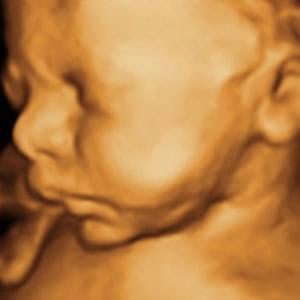

See Your Baby in 3D/4D/HD

With our Customizable 3D/4D/HD Ultrasound Experience for only $99